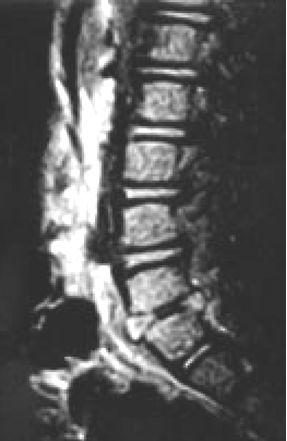

El diagnóstico más probable es discitis L5-S1. Las imágenes por resonancia magnética de la columna, muestra abombamiento tanto anterior y posterior del disco L5-S1, con  erosión de los bordes anteriores, tanto de las vértebras L5 y S1. Existe también evidencia de edema dentro de los cuerpos vertebrales. Las apariciones radiológicas tienen más probabilidades de ser compatible con una discitis suave.

Resonancia Magnética de columna al ingreso.